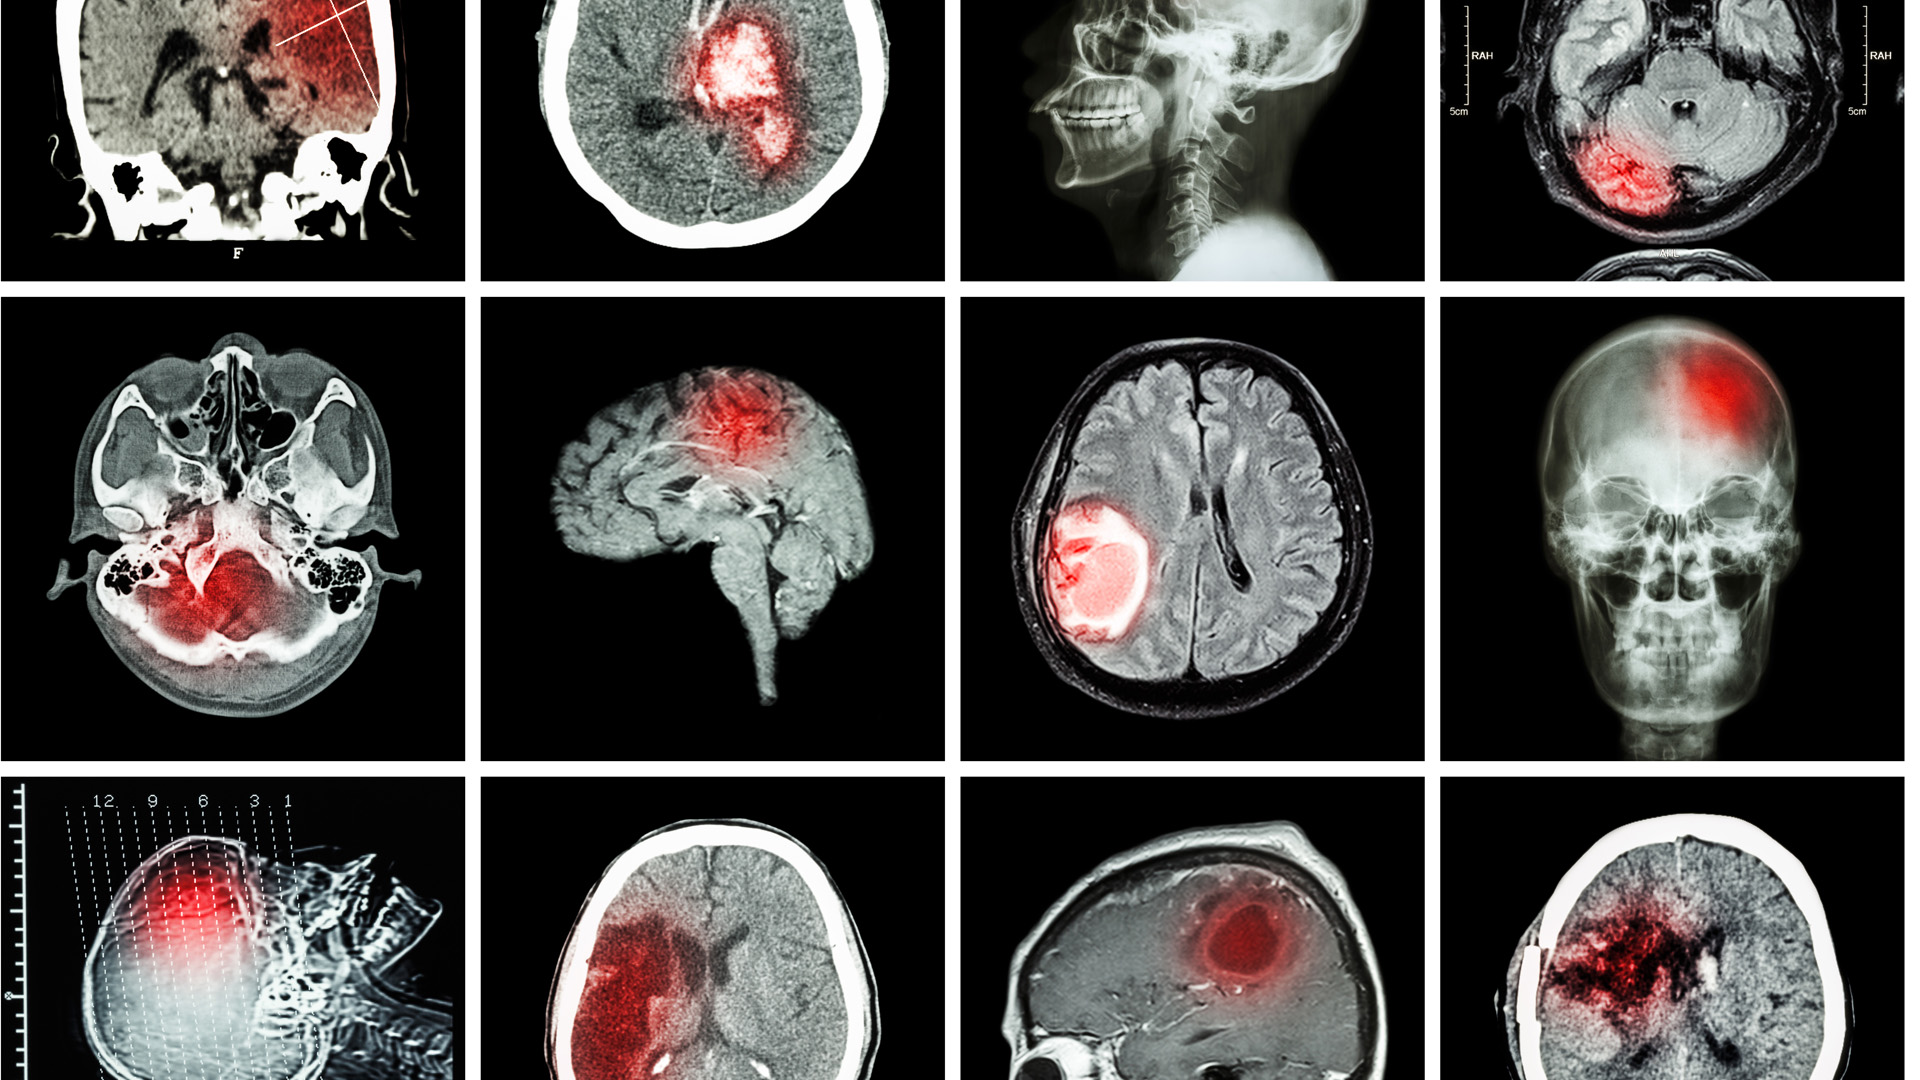

AVC

Au Manitoba, une neurologue s’attaque aux lacunes dans les soins de l’AVC à l’échelle mondiale

La Dre Nishita Singh veut révolutionner la prévention et le traitement de l’AVC